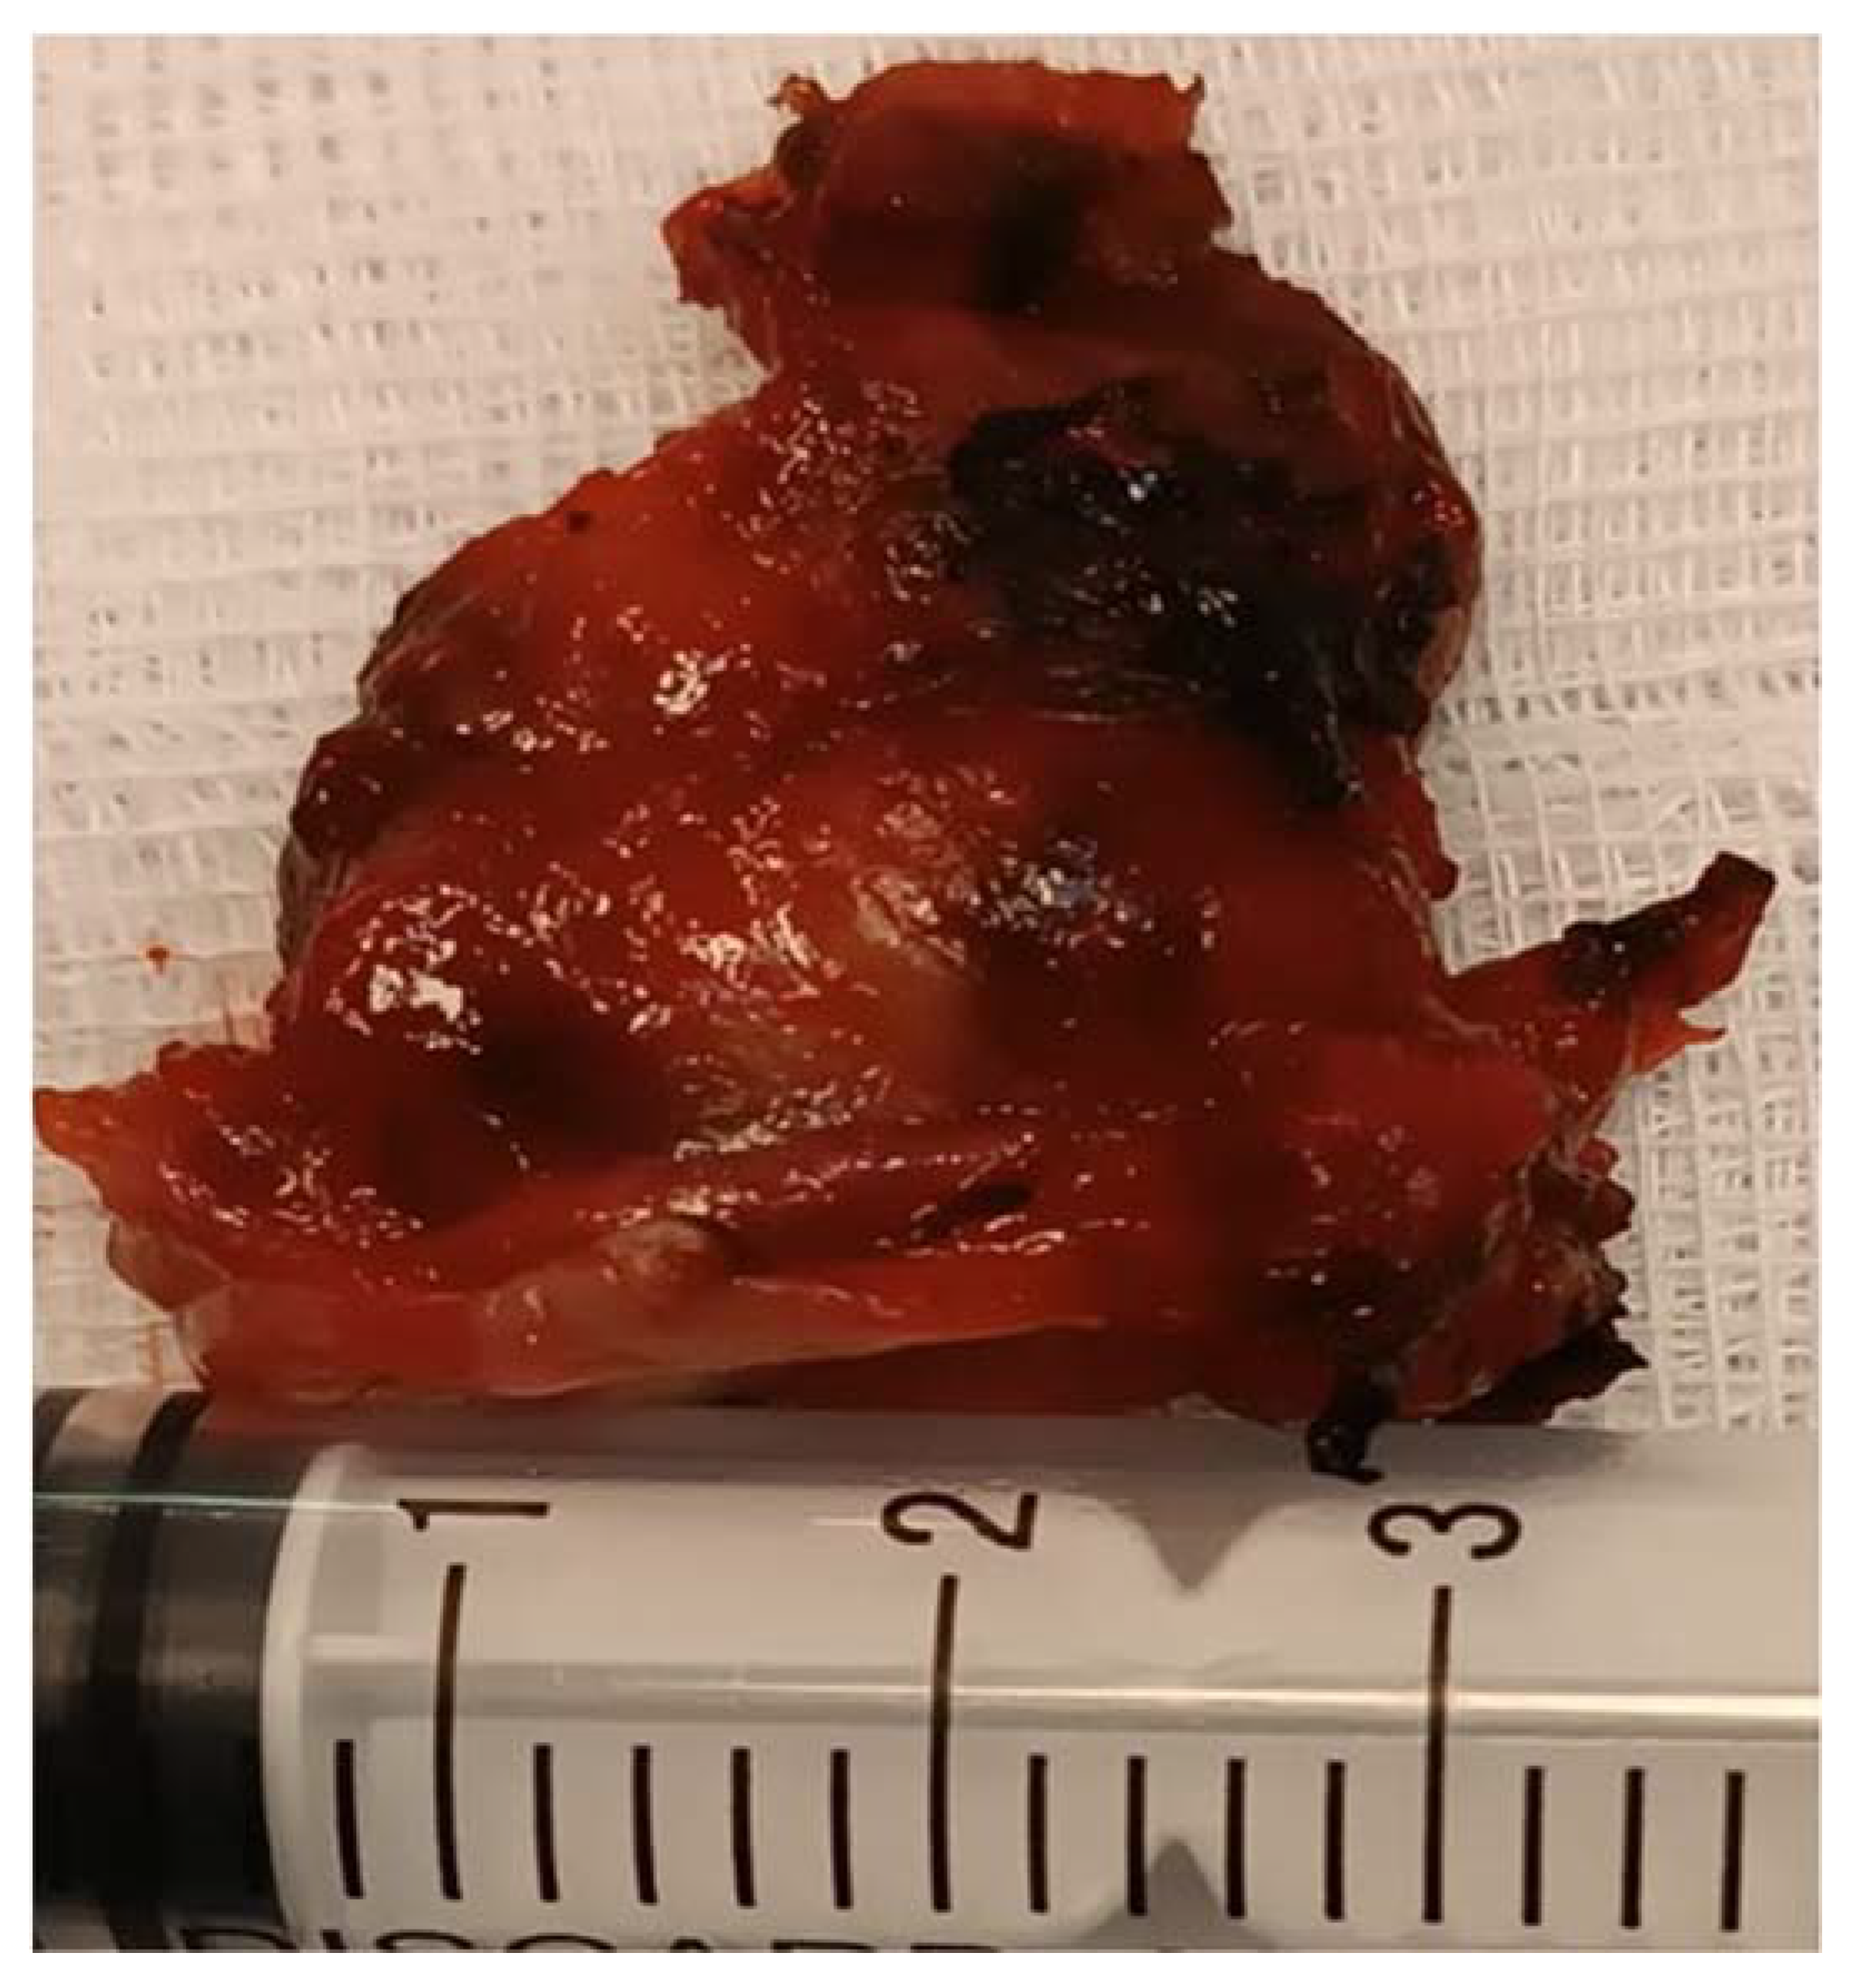

We took multiple pieces from the tumor with the help of a flexible endoscope with a working channel, preserved them in formalin recipient, and handed them to the anatomopatology department. The biopsy revealed the absence of dysplasia, the presence of the “Zellballen” pattern, cubic cells gathered in nest-like groups, rich vascularization, and a Ki67 of 50%, all suggesting a laryngeal paraganglioma (Figure 3).

Figure 3.

Histological aspect of the tumor.